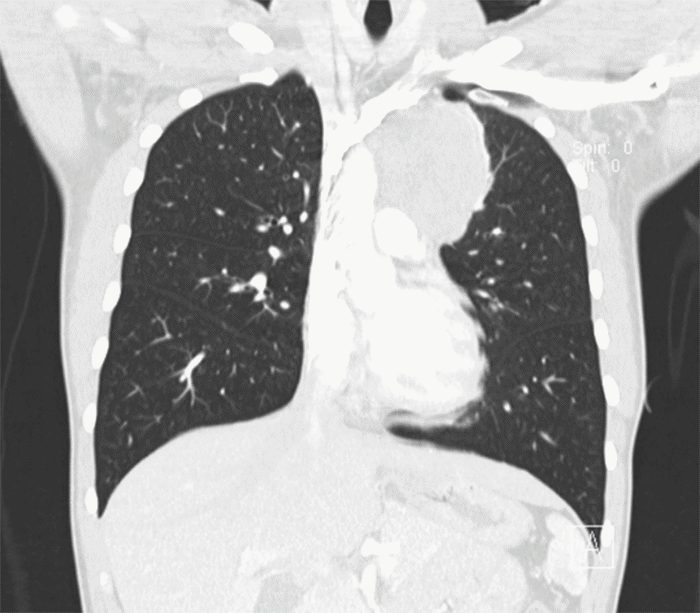

A 20-year-old male presented with dyspnea and chest pain that radiated to the left shoulder and back. He denied fever, cough, nausea, vomiting, night sweats, or weight loss and reported no tobacco or environmental exposures. Laboratory values were all within normal limits apart from an elevated alkaline phosphatase (172 IU/L, normal: 20-140 IU/L). Alpha-fetoprotein marker was found to be 1.20 ng/mL (normal: <10 ng/mL), lactate dehydrogenase (LDH) was found to be 142 U/L (normal: 140-280), and beta-human chorionic gonadotropin (ß-hCG) was negative. Plain radiograph (Figure 1) was significant for a left paratracheal lobulated mediastinal mass causing right tracheal deviation. Chest computed tomography (CT) revealed a large anterior mediastinal mass measuring 8.5 × 8.3 × 7.2 cm (Figure 2 and Figure 3). Scrotal ultrasound revealed no masses, though nonspecific scattered bilateral testicular microcalcifications were noted. A CT-guided biopsy of the mass was performed however was non-diagnostic. Due to a high index of suspicion for malignancy, an incisional biopsy via Chamberlain procedure was performed.

Figure 3. Coronal CT Image. Published with Permission

Mass is shown abutting the thoracic aorta; also no well-defined fat plane between the mass and origin of the left subclavian artery or left common carotid artery